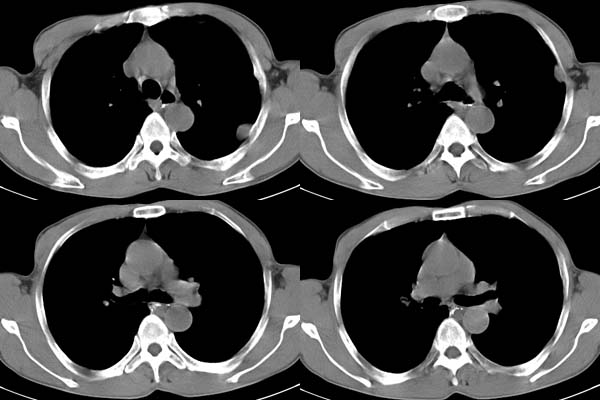

患者,男,65岁,咳嗽,胸痛

ct所见;左下肺可见片状阴影,密度不均,边缘尚清晰,胸膜方向见有条索相连,纵隔窗未见具体结节。左侧胸膜下见多个软组织结节且以宽基底与胸膜相连,右侧胸锁关节层面亦见软组织结节广基与胸膜相连。纵隔未见肿大淋巴结,气管,支气管开口正常。

左肺下叶基底段见结节样稍高密度影,内密度不均匀,边缘不清,可见索条影与邻近胸膜粘连,左侧胸膜上见多个结节影,以宽基底与胸膜粘连.纵隔不宽,内未见明确肿大的淋巴结.